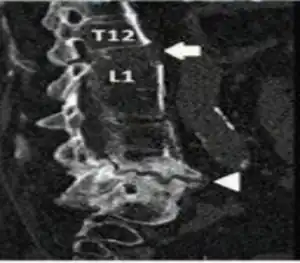

Chalkstick fractures are fractures, typically of long bones, in which the fracture is transverse to the long axis of the bone, like a broken stick of chalk.[1] A healthy long bone typically breaks like a hard woody stick as the collagen in the matrix adds remarkable flexibility to the mineral and the energy can run up and down the growth rings of bone. The bones of children will even follow a greenstick fracture pattern.

Chalkstick fractures are particularly common in Paget's disease of bone, and osteopetrosis.[2] It is also seen in cases of fused spine as in a patient with ankylosing spondylitis.[3]

- ↑ Tomar, SuryapratapSingh (2018). "Chalkstick fracture: A catastrophic injury". Asian Journal of Neurosurgery. 13 (2): 383–385. doi:10.4103/ajns.AJNS_167_13. PMC 5898110. PMID 29682039.